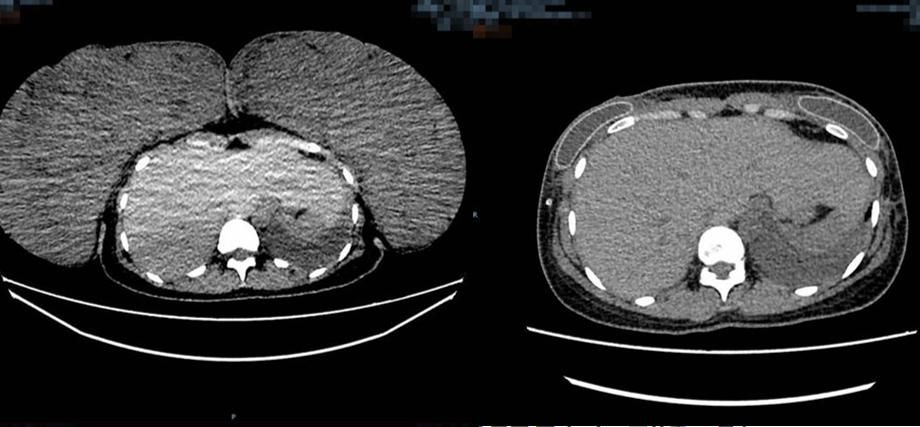

Comparison of the patient's chest enhancement CT. Preoperative size (left): 267 mm×100 mm×293 mm, postoperative size (right): 125 mm×270 mm×340 mm.